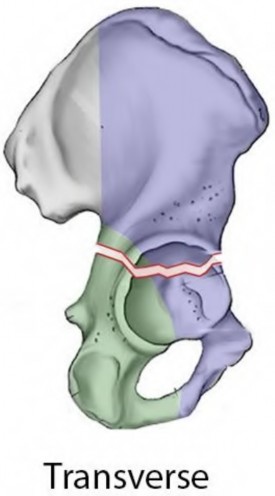

An 80-year-old female presents following a fall from standing. She was an active, independent, community ambulator prior to this event. Past surgical history is significant for a left total hip arthroplasty 10 years prior. A left hip XR is obtained and shown in Figure A. A CT is obtained and demonstrates a displaced transverse acetabulum fracture with medial cup migration. There is no evidence of femoral component loosening or fracture. There is no concern for infection and all inflammatory markers are within appropriate limits. Which treatment is most appropriate?